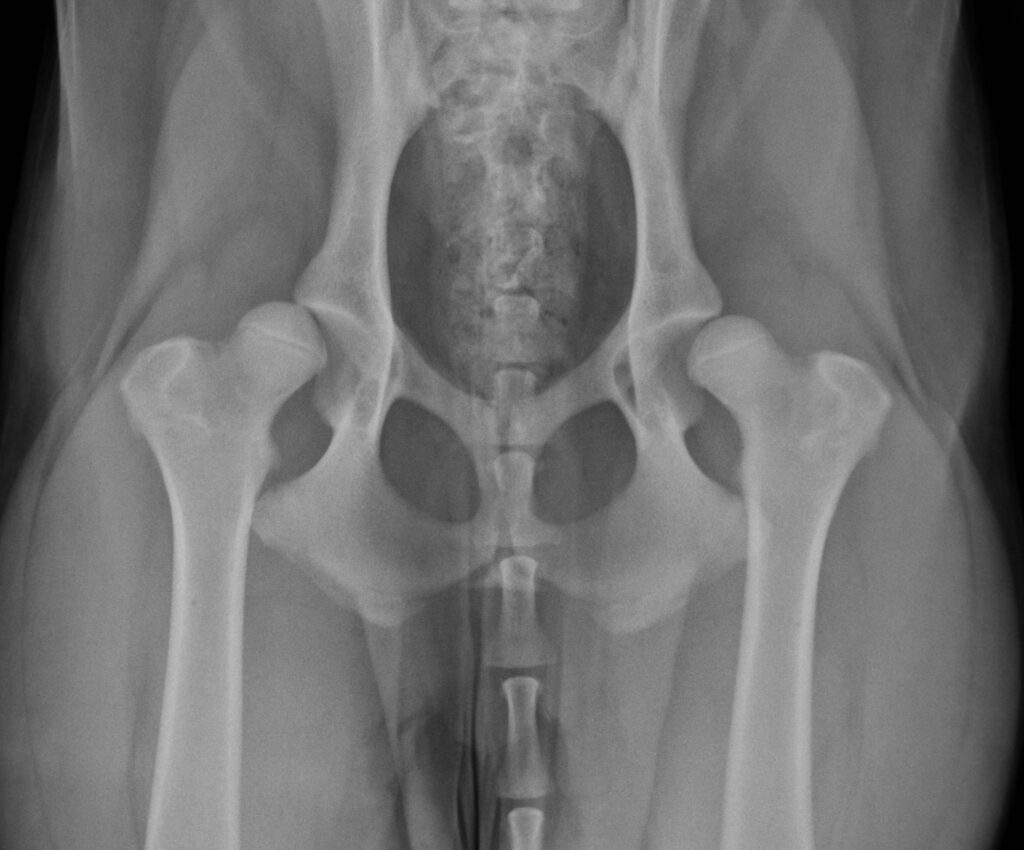

Hind limb

Conditions affecting the hind limb, including the hip, hock, and knee joints.